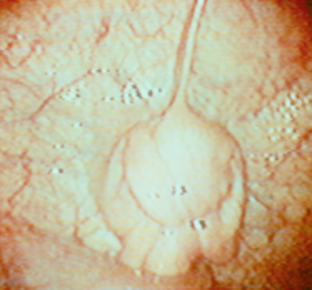

Oviduct pippilae

end oestrus

dioestrus

Healthy endometrium